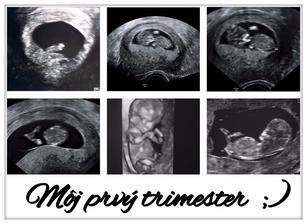

♥ Najkrajších 9 mesiacov ♥

Už teraz viem, že toto bude jeden z mojich najobľúbenejších albumov 🙂 Prípravy na príchod nášho šťastia, rastúce bruško, výbavička a všetko príjemne a pekne spojené s tehotenstvom ♥